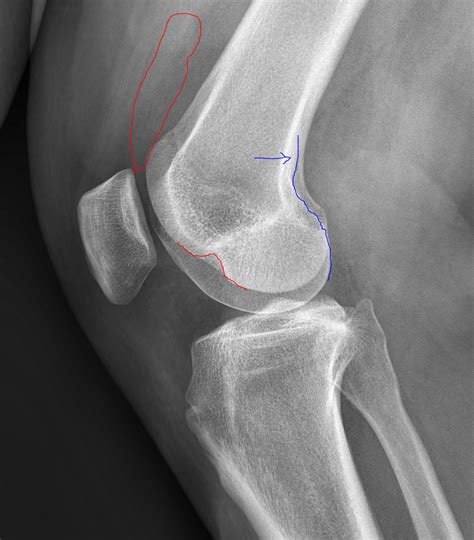

Interpreting a Lateral Knee Xray

Interpreting a Lateral Knee Xray requires a trained eye and knowledge of knee anatomy. Here are some key points to look for:

• Bone Alignment: Ensure that the bones are properly aligned. Any deviation can indicate a fracture or dislocation.

• Joint Spaces: Check the joint spaces for any narrowing, which can suggest arthritis or other degenerative conditions.

• Fractures: Look for any breaks or cracks in the bones, which can indicate a fracture.

• Soft Tissue Signs: While not always visible, soft tissue injuries can sometimes be inferred from the presence of joint effusion or other indirect signs.

Finding Possible Diagnosis

Bone Fracture Fracture of the patella, femur, or tibia

Joint Space Narrowing Arthritis or degenerative joint disease

Misalignment Patellar dislocation or tibial plateau fracture

Joint Effusion Soft tissue injury, such as ligament tear or meniscal damage